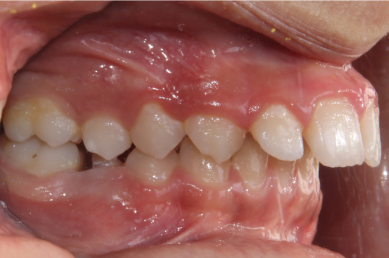

-  دیپبایت، زمانی که دندان های بالایی روی دندان های پایینی شما را زیاد می پوشاند که  این امر معمولا موجب سایش دندانها میشود و حتما باید درمان شود.

-  اپن بایت، زمانی که دندانهای جلویی فک بالا و پایین هیچ همپوشانی ندارند و بین آنها فاصله است. معمولا بیماران اپن بایت با مشکل گاز گرفتن میوه ها و خوراکیها مواجه هستند.